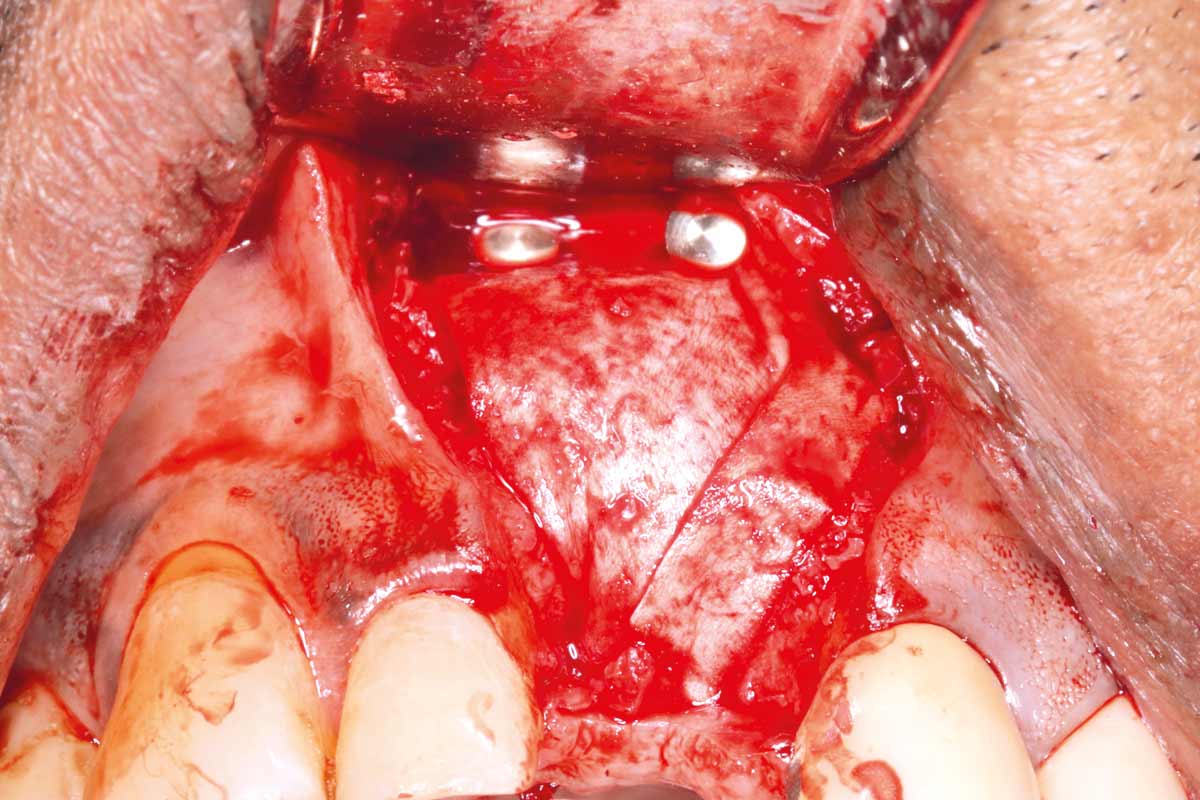

Implant placed in the deficient site. permamem® in place for covering.